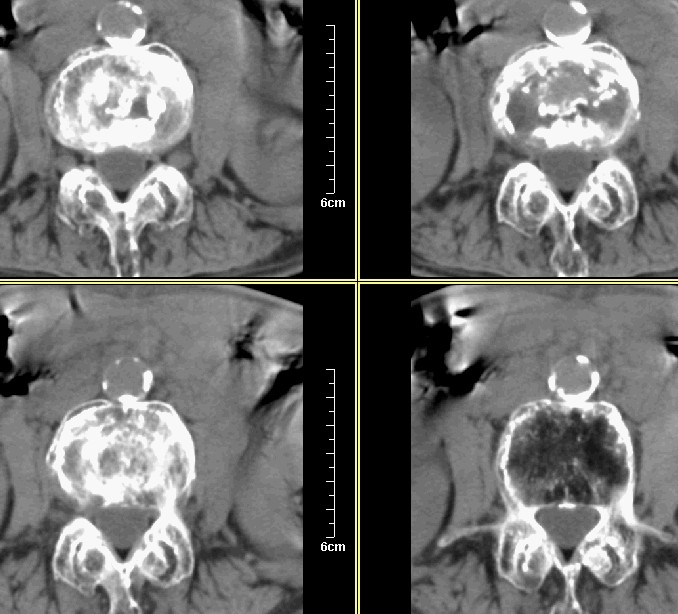

腰1-骶1 间盘及个别椎体扫描

腰3腰4椎体骨质破坏,骨密度低下,骨质疏松,少量骨小梁粗大,紊乱,椎间盘无改变,椎间隙不增宽,椎体无变形,椎旁软组织无肿胀。临床 腰痛明显。考虑:多发淋巴肉芽肿。

支持!几乎累及所有小关节,椎体前缘可见双边影,不排除骨质疏松引起的压缩性骨折。